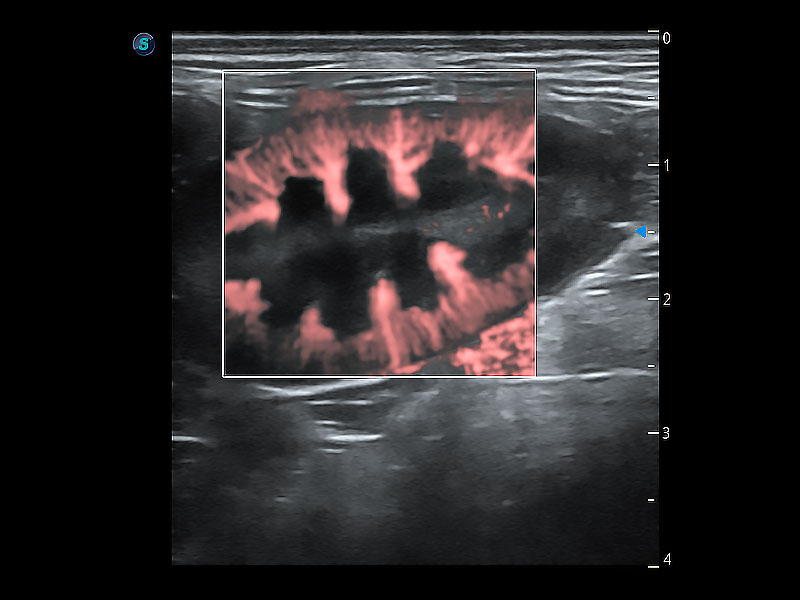

• Bright Flow 立体血流成像

在传统二维血流成像的基础上,呈现血流的立体感,具有动感的生命力之美。即便是微小的血管也能轻松应对,提高了血流的视觉敏感性。

(犬)肠道